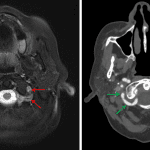

- Focus of restricted diffusion in the dorsal left aspect of the medulla

- Heterogeneous areas of faint restricted diffusion in the left cerebellar hemisphere and left occipital lobe with corresponding patchy T1 signal hyperintensity and susceptibility artifact, more confluent within the left occipital lobe

- Susceptibility artifact associated with vessels overlying the inferior aspect of the left cerebellar hemisphere

- Abnormal flow-related signal in the visualized portion of the extradural left vertebral artery

- T2/FLAIR hyperintensity in the left cerebellar hemisphere extending into the left superior and middle cerebellar peduncles with mild swelling and partial compression of the left lateral margin of the fourth ventricle

- Infarcts with petechial hemorrhage

Small acute/early subacute infarct in the left dorsal aspect of the medulla.

Subacute infarcts in the left cerebellar hemisphere and left occipital lobe with corresponding petechial hemorrhage as well as small hematoma formation in the left occipital lobe. Associated edema and mild mass effect, moreso in the left cerebellar hemisphere with mild mass effect on the fourth ventricle. No evidence of herniation or hydrocephalus.

Abnormal signal in the extradural left vertebral artery concerning for high grade stenosis or occlusion. Susceptibility artifact associated with vessels overlying the inferior aspect of the left cerebellar hemisphere is concerning for thrombus within PICA branches versus elevated deoxyhemoglobin content within cortical veins. Recommend correlation with CTA or catheter angiography.